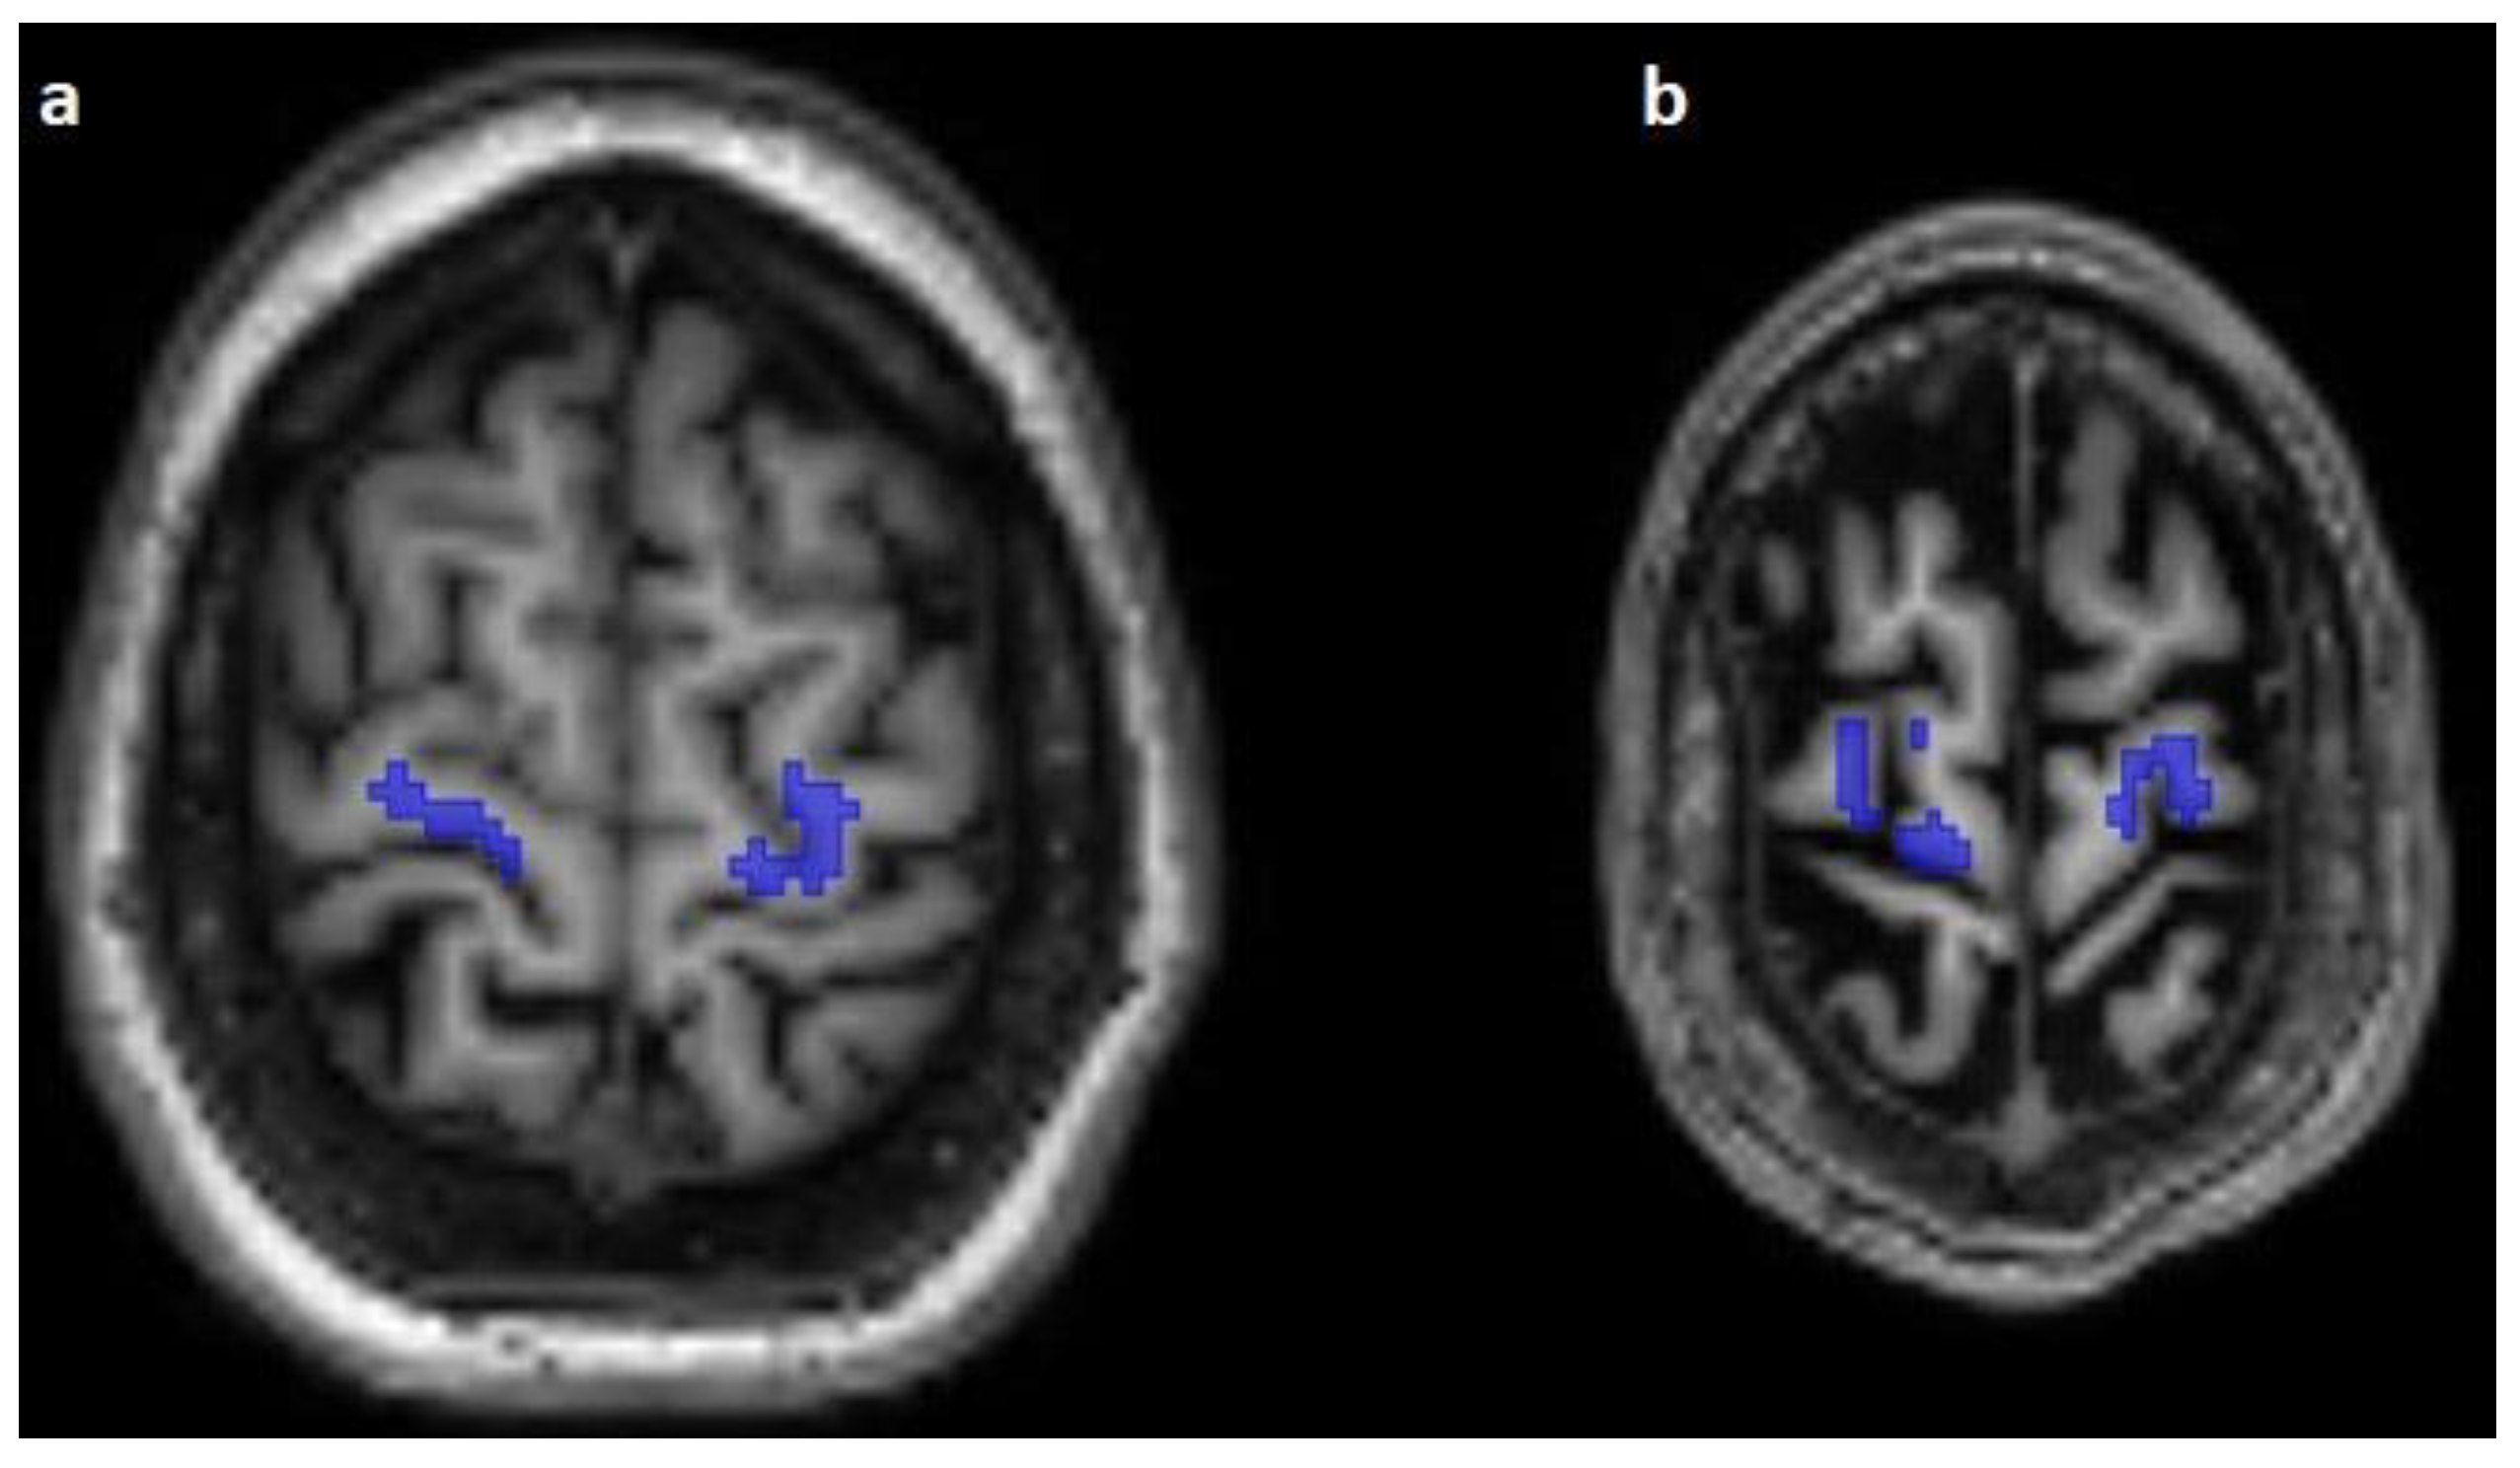

The corticospinal tract traversed the ventral part of the pons in 100/100 cases (100%), traversed the middle-third of the crus cerebri of the mesencephalon in 100/100 cases (100%), traversed the posterior limb of the internal capsule in 100/100 cases (100%), and originated from the medial part of the precentral gyrus in 89/100 cases (89%) (Figure 1, Figure 2 and Figure 3).

Figure 2.

Comparison of the predicted (blue) and reconstructed (red) course of the corticospinal tract on coronal T1-weighted images (a,b).